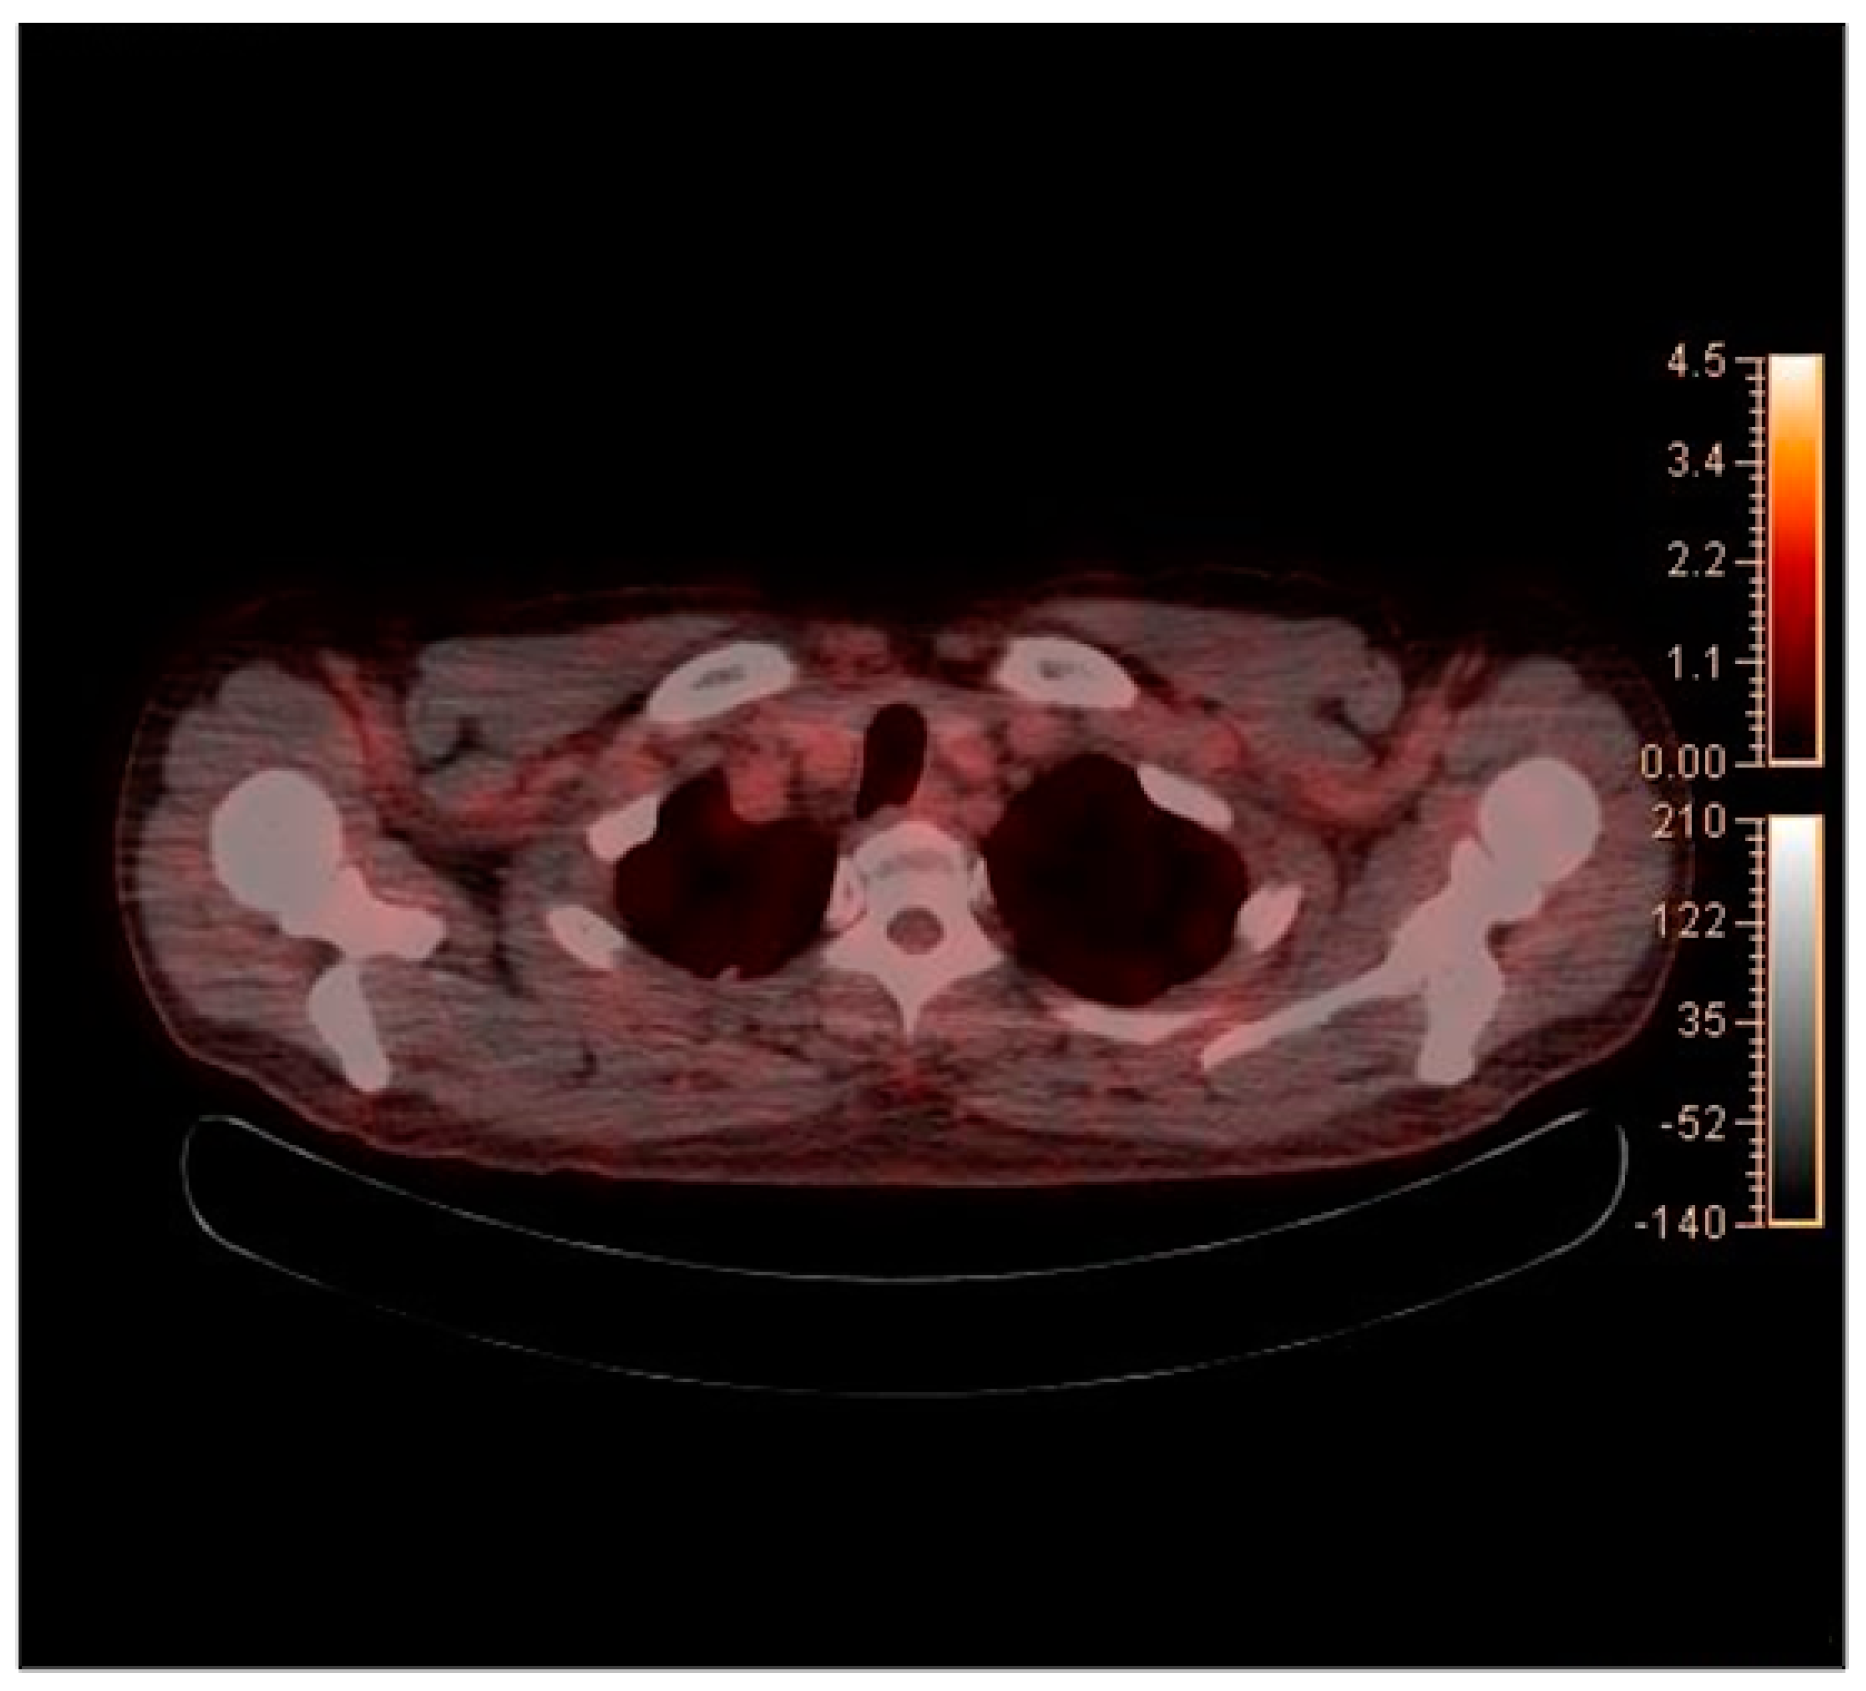

2. Case Report